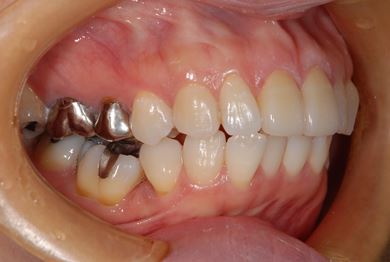

治療前

• 治療前

主訴 上の前歯の歯並びが気になる。

治療方針 セラミック治療により、審美的回復を行う。